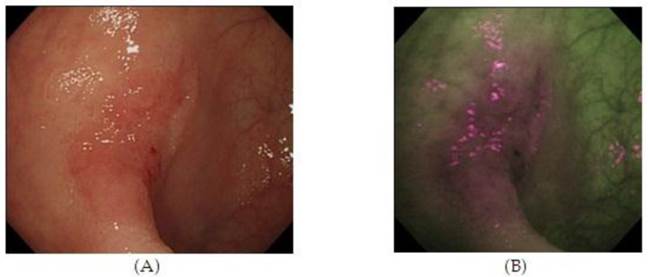

Autofluorescence imaging (AFI) endoscopy uses short wavelengths of light to stimulate endogenous substances, so called 'fluorophores' in the tissue to emit fluorescent light of a longer wavelength. Due to different content of such fluorophores, normal and neoplastic tissues differ in their autofluorescence spectra. Whereas normal mucosa appears green, neoplastic areas are 'flagged up' in violet (Figure 3).53,54 Interestingly, AFI does not detect hyperplastic polyps as a clear magenta area.55 Based on this property, AFI is expected to be used for discriminating colon neoplasms from non-neoplasms, which would be a clear benefit for assessing the scar or staple line from a recently resected colonic neoplastic process. However, studies have not consistently demonstrated the superiority of this method compared with high resolution endoscopy alone, especially for detection of colonic dysplasia.54 Thus, AFI guided biopsies are not currently able to replace random biopsies during surveillance endoscopies, but may be in the future as the technology evolves.

Figure 3

High Resolution Endoscopy (A) and Auto Fluorescence Imaging (B) of a flat and depressed type of colon cancer with submucosal invasion not seen on HRE. 55 (With Permission, InTech Publishing).